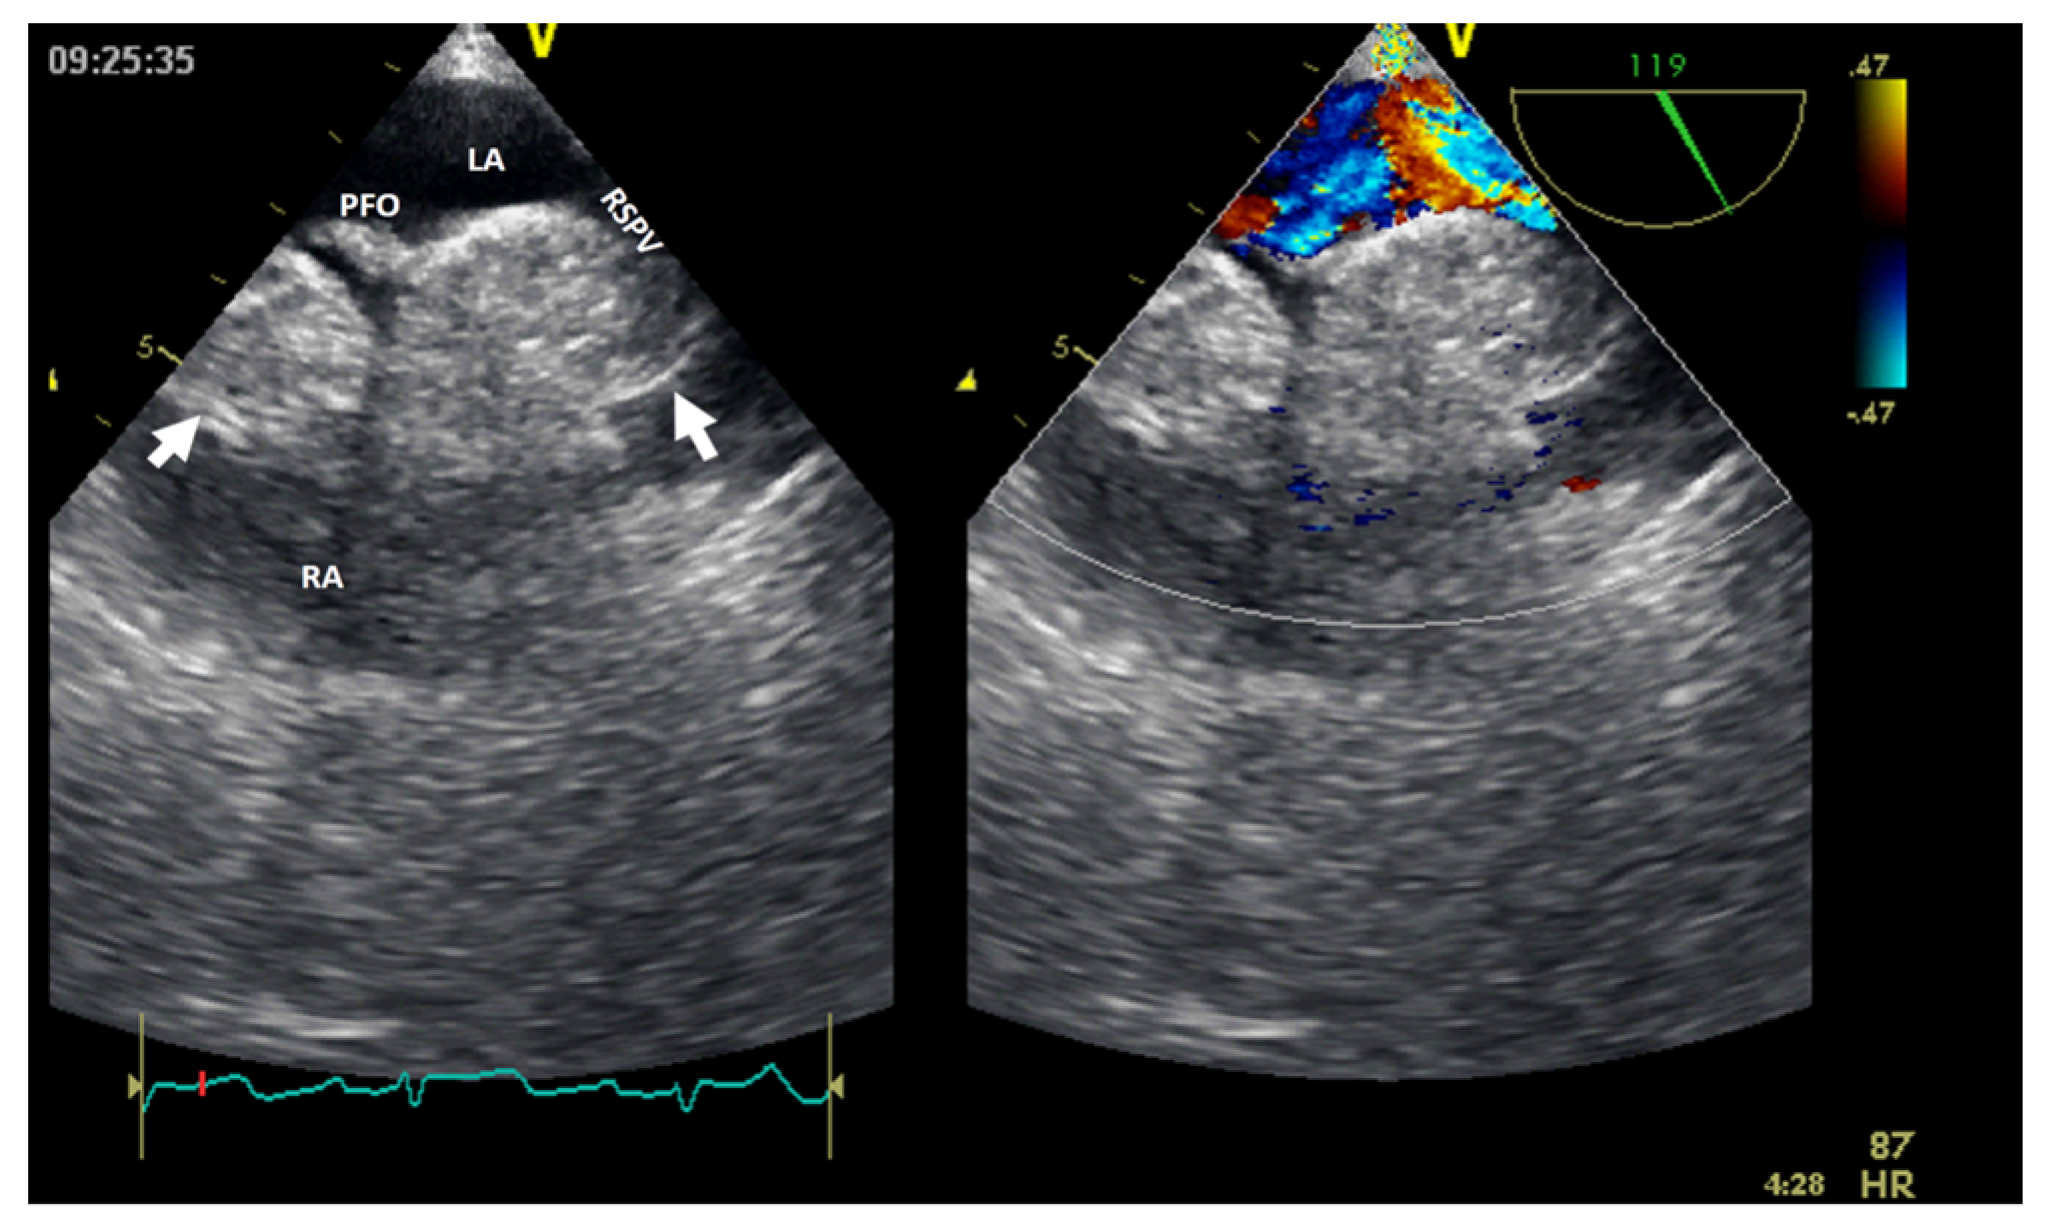

Figure 7.

Two−dimensional transesophageal echocardiography with color Doppler (high transesophageal view at 119°) showing two tumors (arrow) at the level of the interatrial septum with compression on the right superior pulmonary vein (right image). LA, left atrium; LV, left ventricle; PFO, permeable foramen oval; RA, right atrium; RSPV, right superior pulmonary vein.